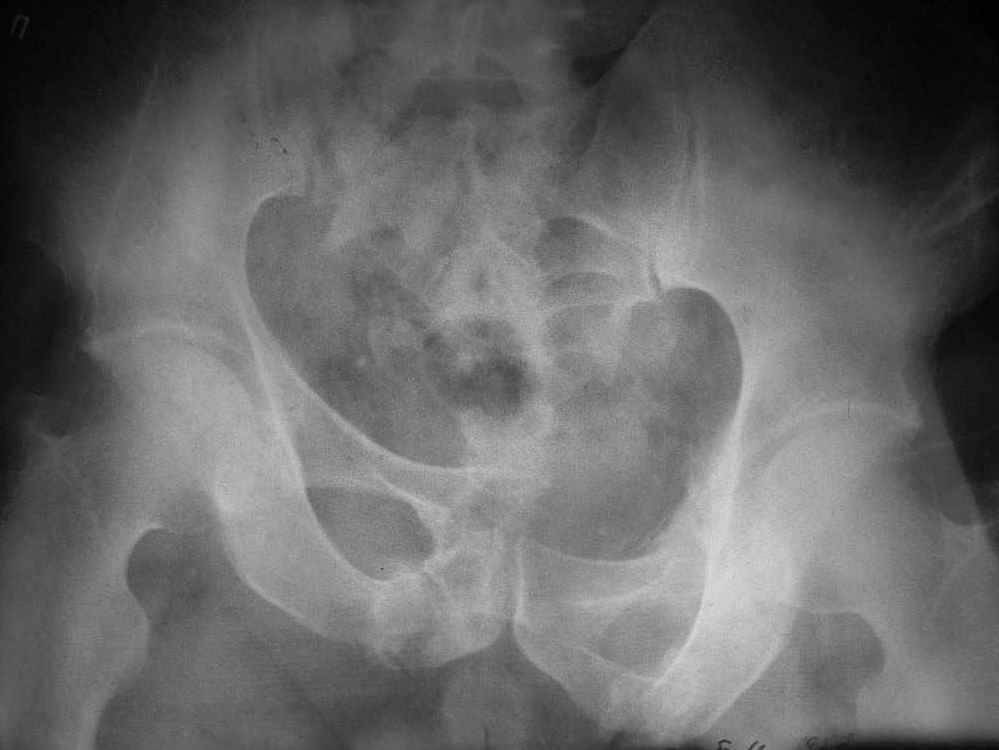

Пример лечения стабильной деформации с вертикальным смещением половины таза.

Исходная картина